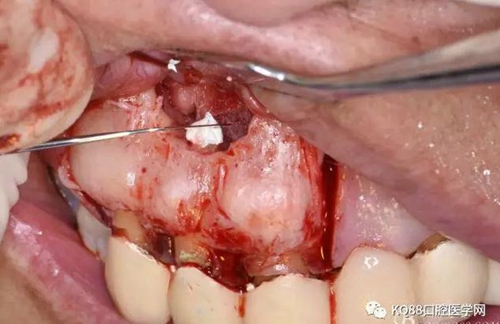

圖10.剝離囊壁

圖11.摘除囊壁后形成的骨腔

圖12.超生骨刀切除12根尖

圖13.根尖倒預(yù)備

圖14.吸潮紙尖干燥根管